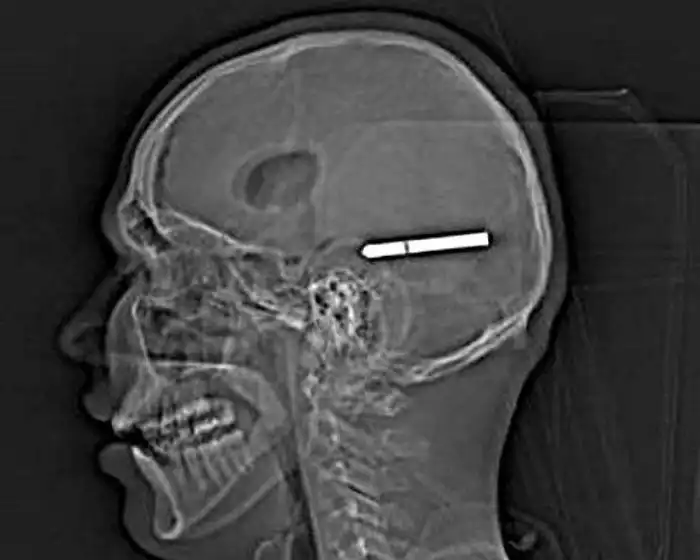

Необычные предметы в теле людей на рентгеновских снимках

На рентгеновских снимках людей порой можно обнаружить самые необычные предметы, которые находятся в их теле.

Еадо свой снимок выложить. У меня в ноге и саморез и спица и скобы!

Человечество явно с гвоздями не дружит!!! Что не снимок то гвоздь в башке!